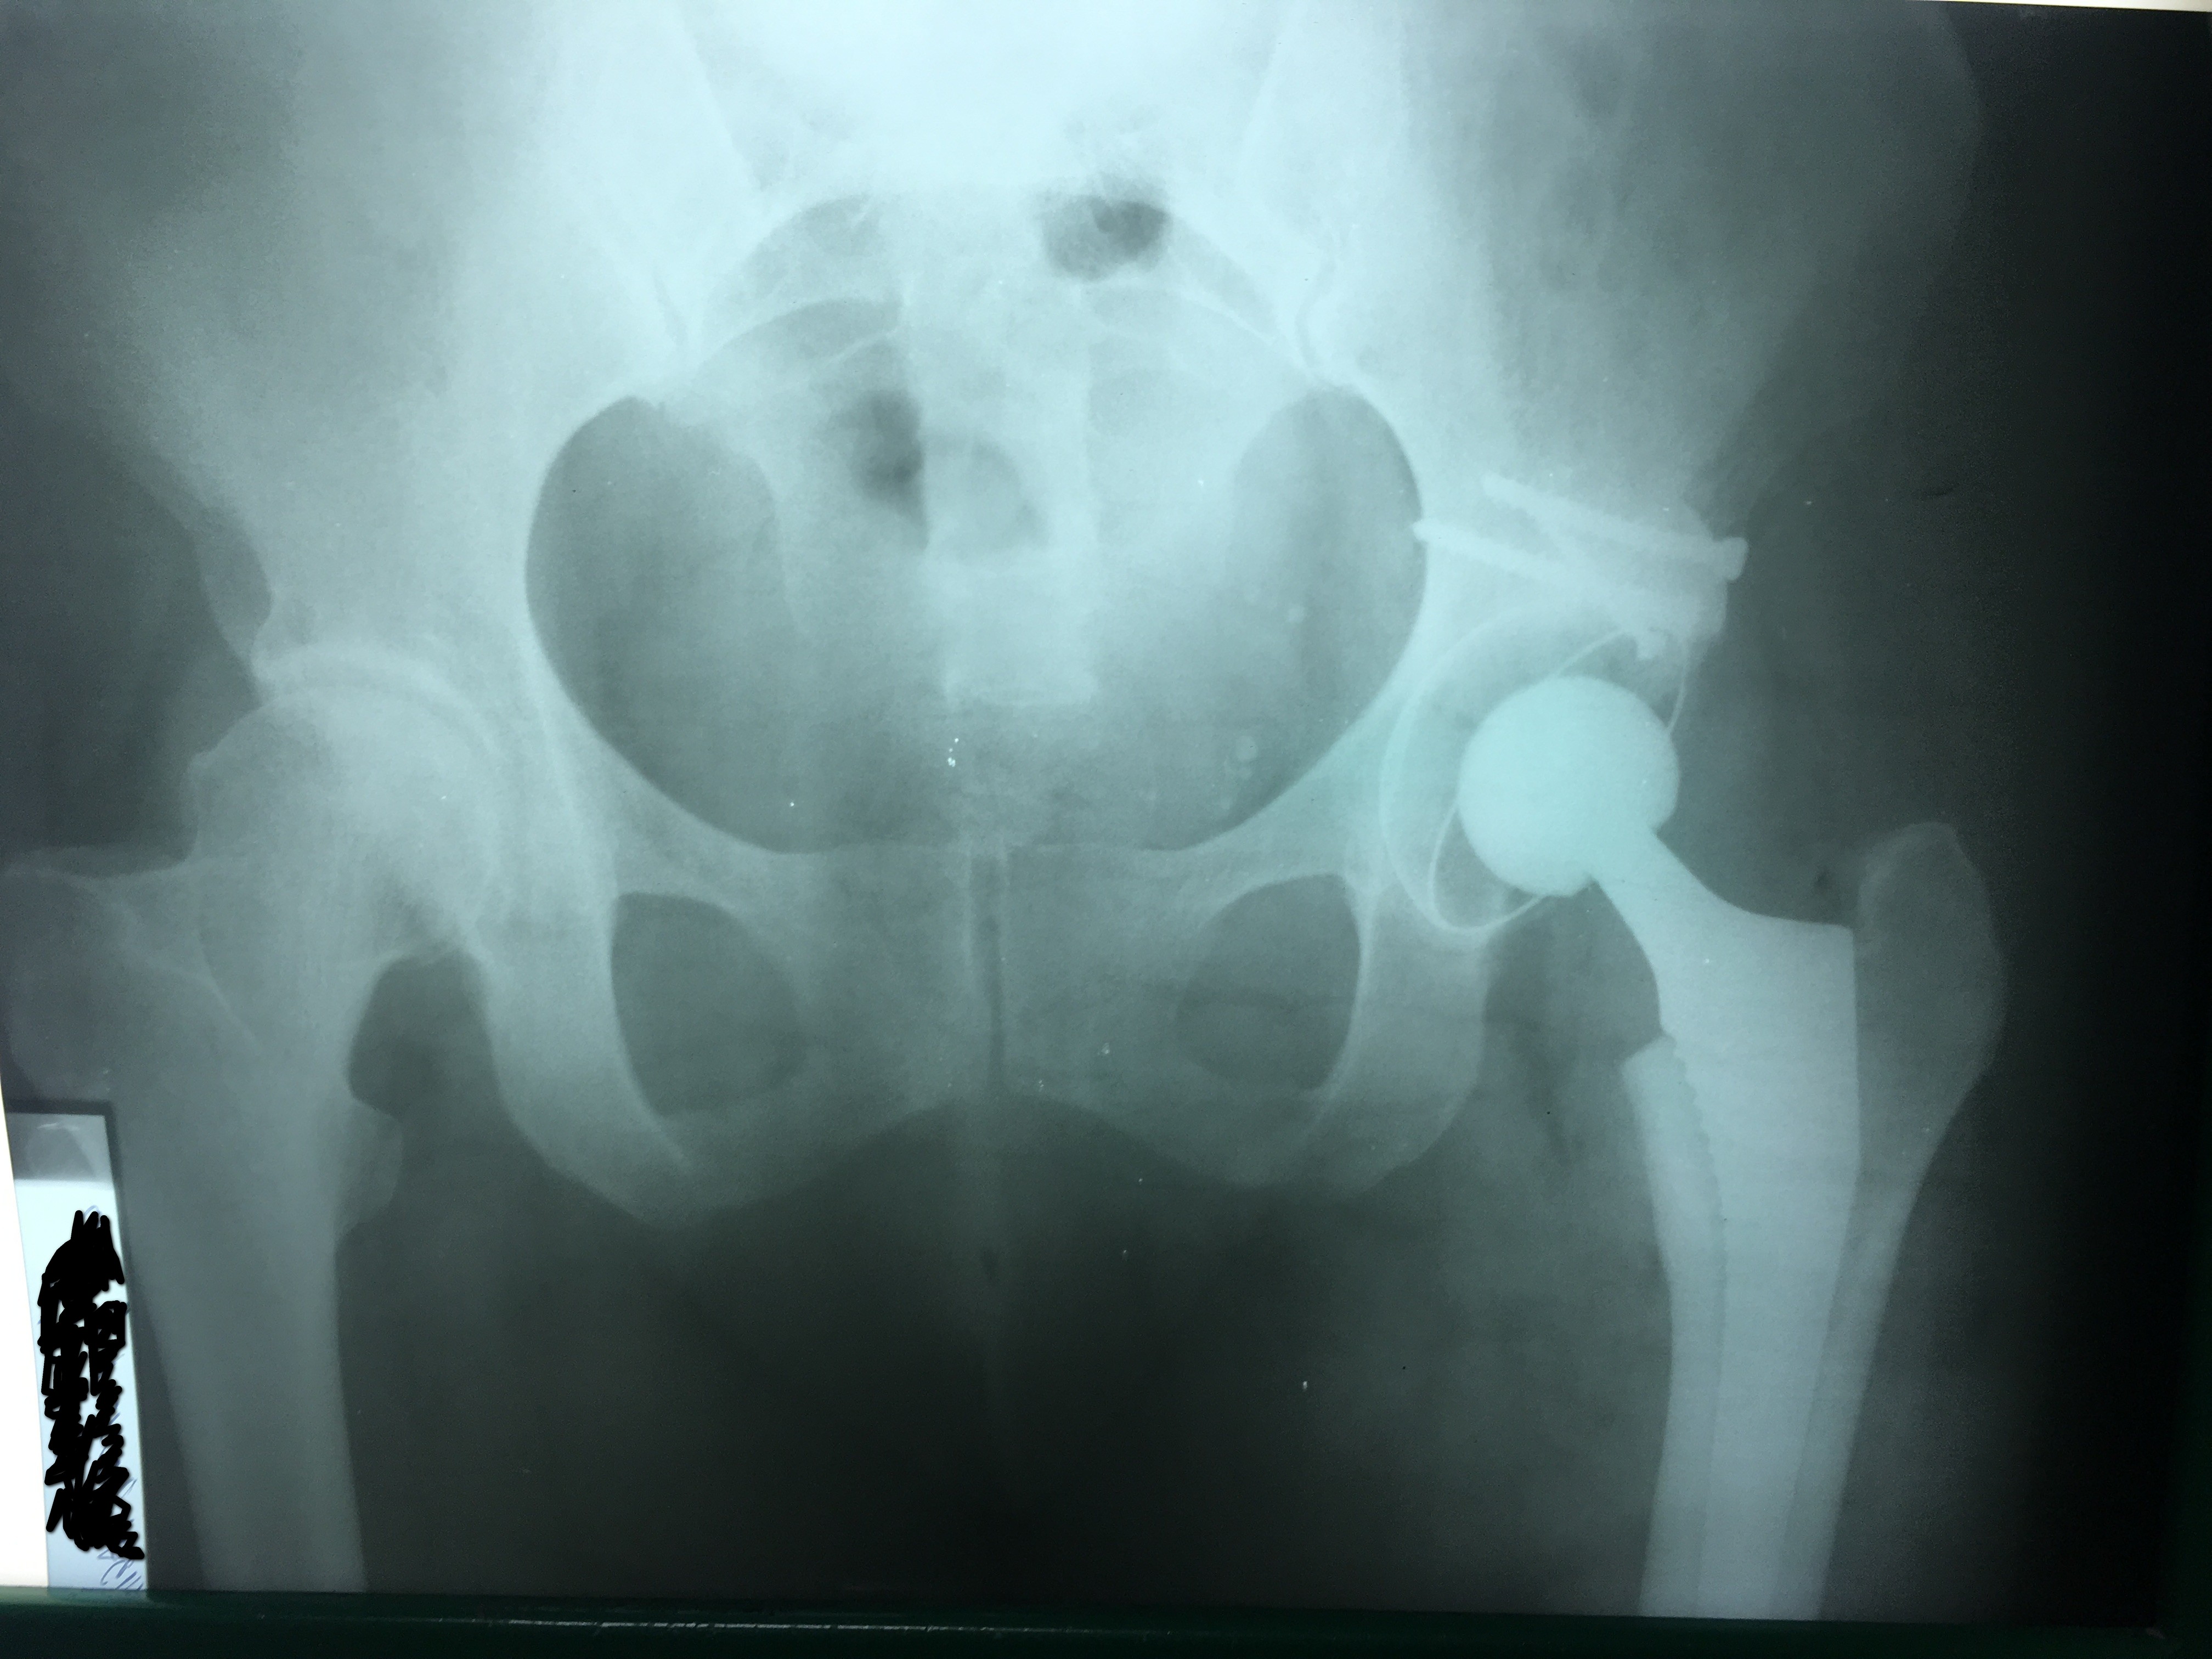

Эндопротезирование тазобедренного сустава